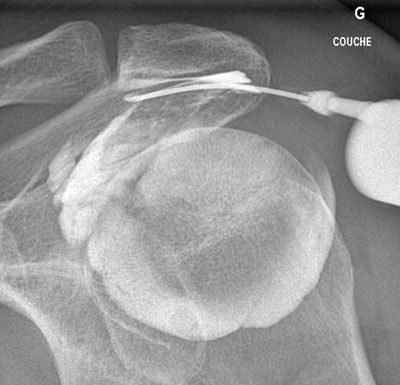

Infiltration de l'articulation omo-humérale (épaule).

Après ponction directe de l'articulation, il est injecté du produit de contraste afin de s'assurer de la position intra-articulaire de l'aiguille avant d'injecter l'anti-inflammatoire.